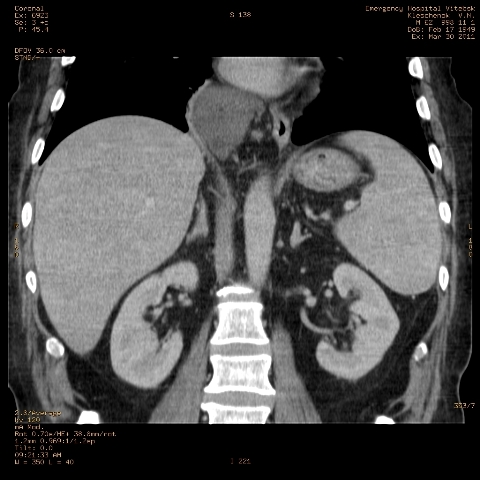

при исследовании органов брюшной полости по поводу абсцесса печени, в нижнем этаже средостения выявлено образование неоднородной плотности (-5-+25), при в/в контрастировании - не контрастируется, при per os - затёков из пищевода нет, неправильно овальной формы. предположительно киста перикарда? спасибо за помощь!

Может быть enteric duplication cyst. Как бы есть грыжа жира hiatal. И что с печенью? Мало срезов.